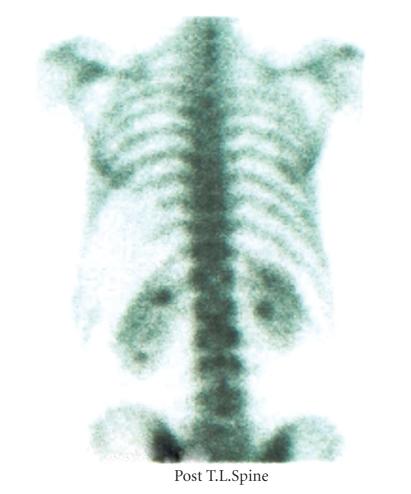

Unlike other soft tissue sarcomas, myxoid/round cell liposarcoma (MRCL) has a tendency to spread to extrapulmonary sites but bone metastases are thought to be uncommon. In case reports, negative bone scintigraphy has been noted in patients with myxoid/round cell liposarcoma and bone metastases but the prevalence and optimal method of diagnosis of bone metastases in this common subtype of liposarcoma are unclear. In an attempt to answer these questions, data were obtained from a prospective database of patients with sarcoma, including MRCL, and the diagnostic imaging used was examined. A variety of imaging tools were used including plain X-rays, bone scintigraphy, computed tomography (CT), and magnetic resonance imaging (MRI). Eight patients (4.3%) developed skeletal metastases all of which were positive on MRI. Bone scintigraphy was negative in two out of four cases, CT was negative in six out of seven, and X-rays were negative in four. Radiography and CT measure mainly cortical bone involvement, whereas MRI examines bone marrow. When investigating patients with MRCL for bone pain, negative X-rays and bone scans do not rule out bone metastases. In our experience, MRI provides the most sensitive technique for the diagnosis of bone metastases in MRCL.

与其他软组织肉瘤不同,黏液样/圆形细胞脂肪肉瘤(MRCL)有扩散至肺外部位的倾向,但骨转移被认为并不常见。在病例报告中,黏液样/圆形细胞脂肪肉瘤伴骨转移的患者骨闪烁扫描结果为阴性,但这种常见脂肪肉瘤亚型中骨转移的发生率及最佳诊断方法尚不清楚。为回答这些问题,我们从一个包括MRCL在内的肉瘤患者前瞻性数据库中获取数据,并对所使用的诊断性影像学检查进行了分析。我们使用了多种影像学工具,包括普通X线、骨闪烁扫描、计算机断层扫描(CT)和磁共振成像(MRI)。8例患者(4.3%)发生了骨转移,所有病例的MRI检查均为阳性。4例中有2例骨闪烁扫描结果为阴性,7例中有6例CT检查结果为阴性,4例X线检查结果为阴性。X线摄影和CT主要检测皮质骨受累情况,而MRI检查骨髓。在对有骨痛的MRCL患者进行检查时,X线和骨扫描结果为阴性并不能排除骨转移。根据我们的经验,MRI是诊断MRCL骨转移最敏感的技术。